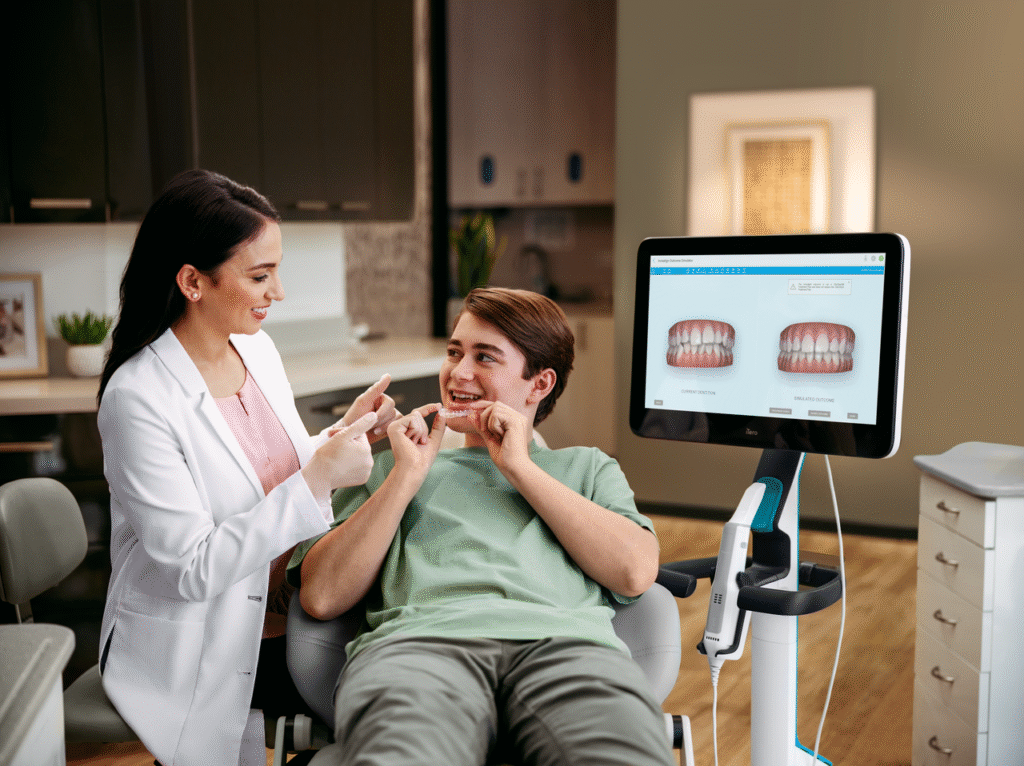

We now use digital scanners to take precise measurements of the teeth. This process is fast and accurate, creating a digital model of the teeth on a computer. It helps us prepare and set up Invisalign aligners in just one day.